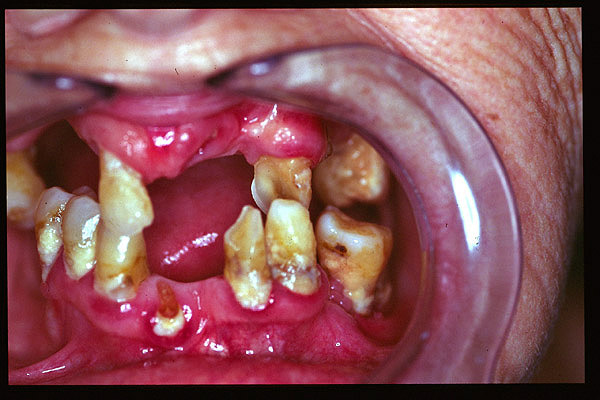

CM Edentulismo parcial. Restos radiculares. Placa bacteriana